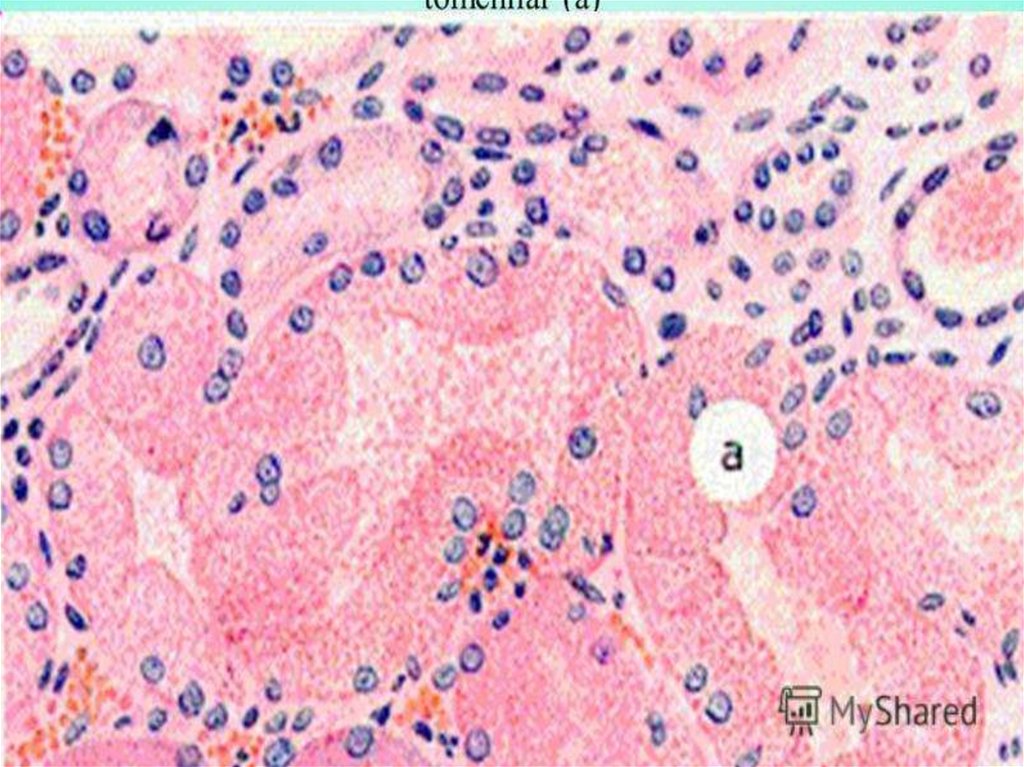

Нарушение обмена гликогена

а

Углеводная дистрофия

эпителия почечных

канальцев (при

сахарном диабете)

а)

б

В клетках эпителия

видны

скопления

гликогена

б) В просвете

канальцев

крупные гранулы